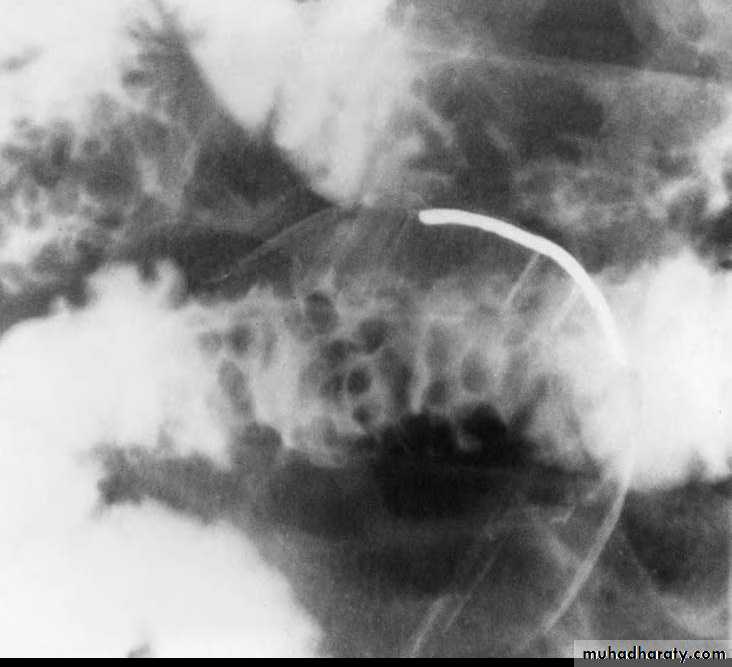

c. Due to bowel wall thickening, the folds may be thickened, distorted or disappear & the loops may be separated in severe wall thickening. With inflammatory mass, greater displacement of loops is seen.Mucosal fold thickening, ulceration, nodularity, asymmetric bowel wall

involvement, regions of narrowing, and separation of small bowel loops are present.d. Fistulae to the other loops of SB, colon, bladder or vagina.